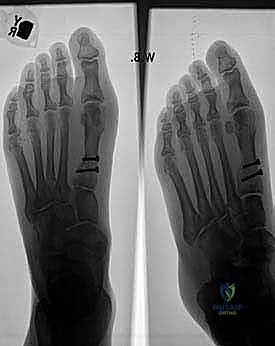

C. Internal Fixation

"Once we're satisfied with the reduction and the IMA is optimized, we'll proceed with internal fixation. We'll use two 2.7-mm cortical screws (Synthes, Paoli, PA) inserted in a lag screw fashion from the lateral to the medial cortex."

- Screw Insertion: "Insert the two 2.7-mm cortical screws. Tighten them sequentially, observing the compression across the osteotomy. While the small size of the proximal fragment often doesn't allow both screws to be perfectly parallel to the osteotomy, this isn't critical because the primary compression has already been achieved with our reduction clamp."

TECH FIG 3 • A. Compression with the clamp “greensticks” the medial cortex. B, C. Two screws are inserted in a lag screw fashion. D. The capsule is repaired. The skin is closed.

* Final Fluoroscopic Check: "Before we close, let's get a final set of image intensification views. We need to confirm the reduction in the IMA, satisfactory placement of our screws, and the desired relocation of the sesamoids beneath the first metatarsal head. This is our last chance to ensure everything is perfect."

FIG 2 • A–D. Preoperative and postoperative radiographs.